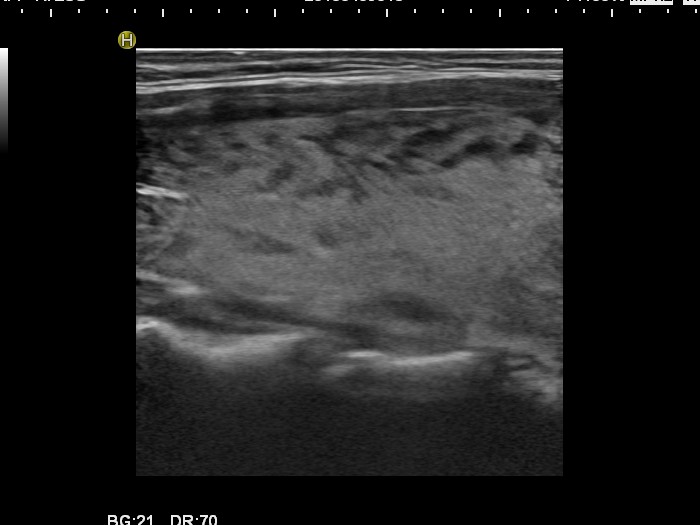

Graves' disease - Case 15.

Follow-up investigation 30 months after first visit (ultrasonographic picture 2)

Patient one year after discontinuation of thyrostatics in hyperthyroid state

Right lobe, longitudinal scan.